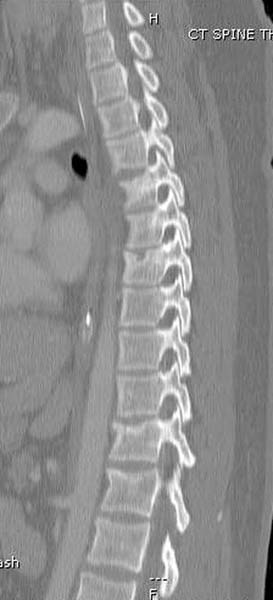

> Вообщем.., больная поступает около 2.00 дня и дальнейщая хронология: 2.27

> PМ рентген грудной клетки; 2.54 РМ рентген бедра; 2.53-3.06 КТ скан, всего

> Перелом позвоночника и боковую компрессию таза отнесли к стабильным

> переломам и не стали форсировать события до лучших времен...

> После спадения отека на стопе произведена фиксация тарана. Кстати, коллеги

> пересмотрели первоначальную консультацию по позвоночнику и на двух уровнях

> провели фиксацию. Из-за длительного постельного режима без нагрузки таз не

> стали оперировать...